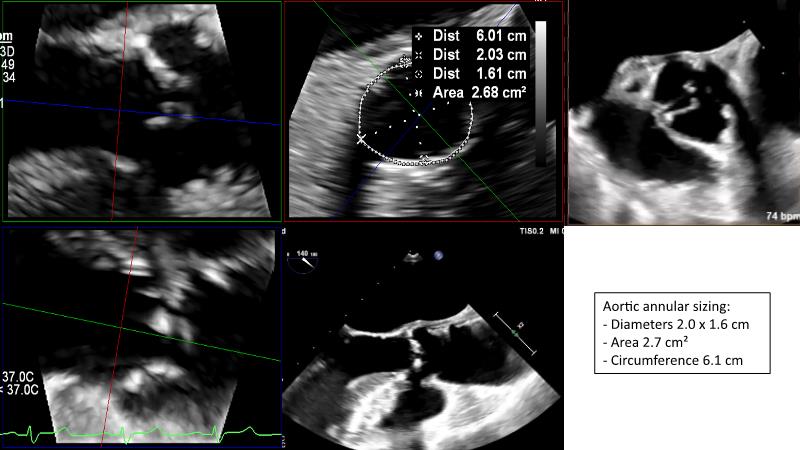

The primary focus of this GulfPCR-GIM 2023 session revolves around pre-procedural planning considerations, valve selection, and managing complex anatomies using both traditional self-expanding valves and the Evolut FX system. Additionally, the session aims to explore the work-up protocol for patients grappling with severe AS and advanced CKD, elucidate the algorithm for selecting the appropriate TAVR platform, discuss strategies to reduce contrast utilization, and highlight the distinctive advantages offered by the Evolut FX system.

• To discuss challenges in TAVI procedural planning

• To discuss valve choice in challenging anatomies